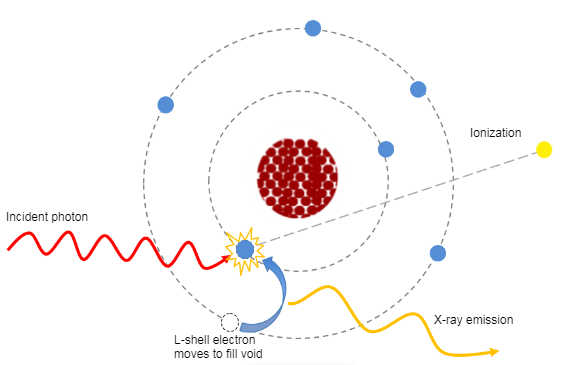

Attenuation is one of the physical principles of radiation interaction. If you recall, it is the reduction in the number of x-ray photons in the beam, and the subsequent loss of energy as the beam passes through the matter (or patient in this instance). In CT, as in diagnostic radiology, the attenuation is dependent on the type of tissue being scanned, such as the soft tissue, the bone, the blood or the muscle. Each type of tissue attenuates a different amount of photons which results in image differences on the finished scan. The denser the tissue, the more the attenuation of the beam.

Let us now look at how the attenuation in a CT scan is measured.